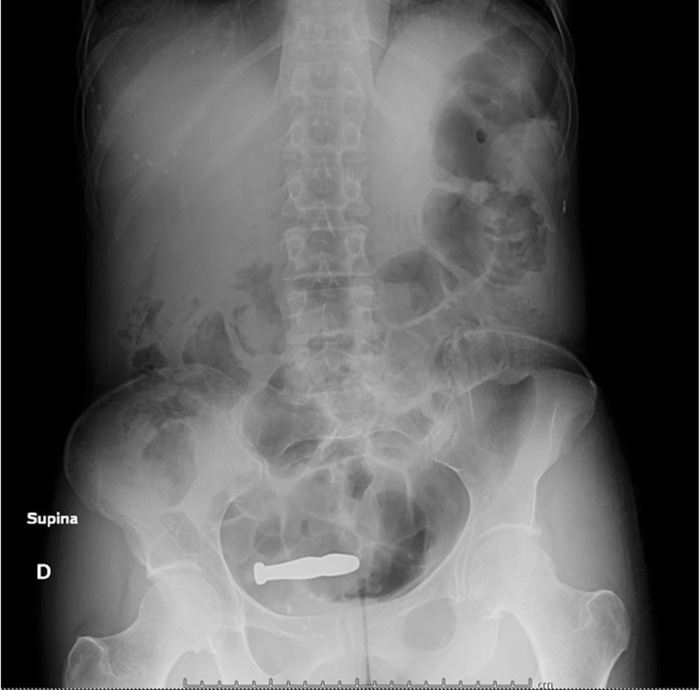

На рентгенограмме таза четко визуализировалось наличие объекта высокой плотности, по форме напоминающего винтовочную пулю длиной около 6 см, расположенного наискось над лобковым сочленением.

Рентгенолог определил его как «вероятно внутриматочное устройство».

Figure 2. Рентген на котором четко видно наличие рентгеноконтрастного объекта в форме пули над лобковым симфизом.